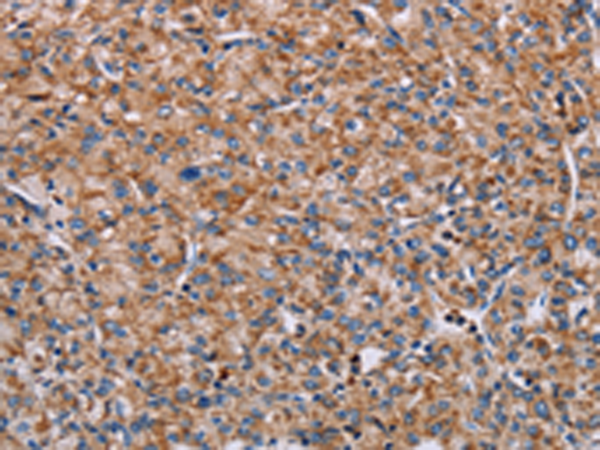

分类: 科研抗体货号: P10851别名: EVEC; UP50; ADCL2; ARMD3; DANCE; ARCL1A; FIBL-5; HNARMD应用: IHC反应种属: Human, Mouse, Rat